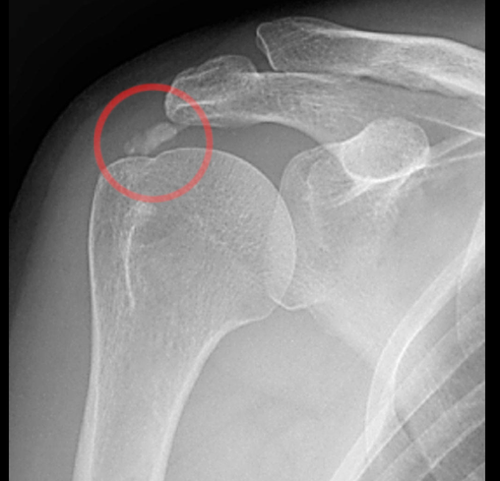

Les pathologies liées à l’épaule

Selon la pathologie affectant l'articulation de l'épaule, les options thérapeutiques, qu'elles soient médicales ou chirurgicales, seront abordées lors de la consultation, en tenant compte de vos examens médicaux et de vos attentes fonctionnelles.